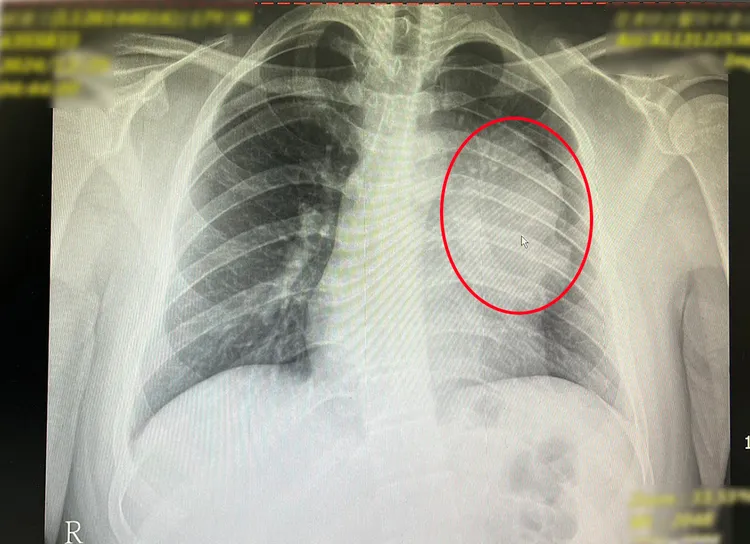

少年胸腔有1顆12公分大的縱膈腔精細胞瘤。中港澄清提供

中港澄清醫院表示,這名少年平時毫無症狀表現,卻在學生健檢的X光檢查結果顯示異常,去年12月接獲通知後,立即轉診來中港澄清醫院胸腔外科,經賴重佑部主任確認在前縱膈腔偏左,有一顆12公分且高度疑似為惡性的腫瘤。

院方先安排患者入院檢查,包括做切片先確認腫瘤性質,接著進行胸部核磁共振造影以確定沒有侵犯心包膜,及腫瘤與心臟、肺臟的黏著程度。另外考量腫瘤疑似生殖細胞瘤,也做了腹部斷層掃描,確認肚子沒有其他腫瘤存在,在一連串深度檢查後確定是罕見的縱膈腔精細胞瘤。

賴重佑部主任說明,這種巨大腫瘤治療前一定要先取得病理組織診斷,如果是淋巴癌則建議採化學治療,因此並非每個案例都建議開刀。而這位患者後續因器官沾黏相當嚴重,在完善治療計畫考量之下,決定改以傳統正中胸骨切開進行腫瘤的切除,犧牲了一條上肺靜脈的分支,將12公分的腫瘤連帶部分左肺做移除,最後腫瘤重達550公克。